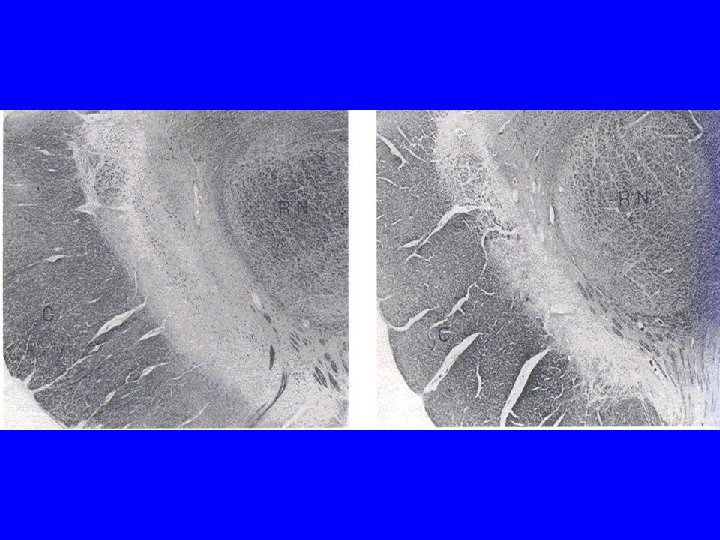

Pathology of Parkinson’s Disease

Pathophysiology of Parkinson’s Disease

Main Biochemical Abnormality • Marked striatal DA depletion – “Striatal dopamine deficiency syndrome” • • At death, DA loss > 90% <50% DA loss is asymptomatic ~70% DA loss for symptom manifestations Severity of DA loss best correlates with bradykinesia in PD